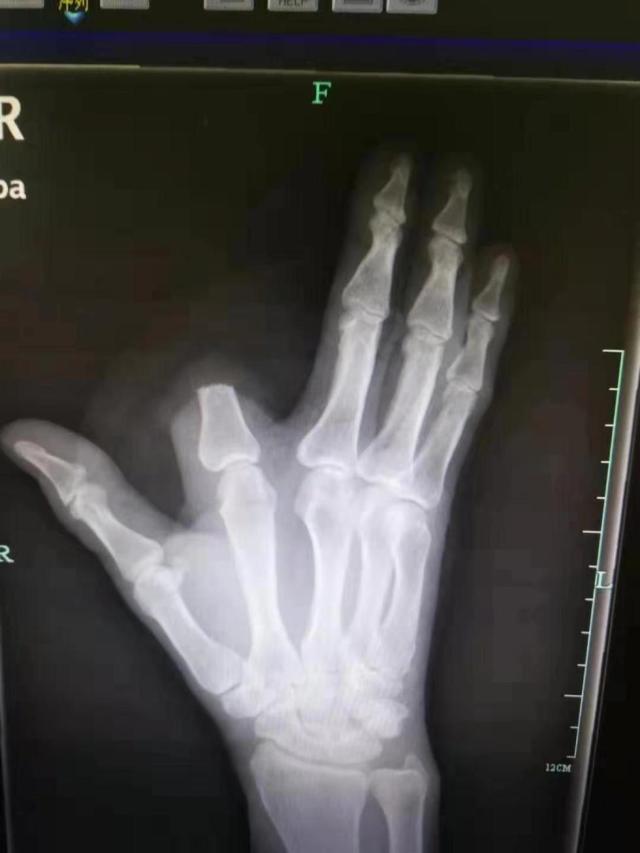

其实单纯从毒性来说,五步蛇的蛇毒并不是很厉害,但是人家的剂量大啊。中国致死率第一的毒蛇不是它,但是说到致残率它可就厉害了,不少人被咬了之后没有及时就医,导致需要进行截肢手术。那么我们被五步蛇咬了该怎么办呢?

被五步蛇咬了之后,大家一定要镇定,不要自己吓自己,大部分情况下及时就医是可以治好的,不要心一狠,直接自己就给自己截肢了,那样后悔就来不及了。杭州一男子张先生在山上干活时被毒蛇咬伤了,在发现是五步蛇之后,他居然直接拿刀砍掉了自己一部分的食指。